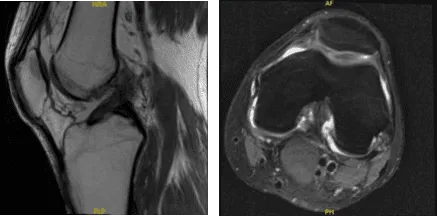

En su resonancia, el resultado mostró una morfología anormal del LCA, probablemente relacionada con una alteración parcial o posiblemente una alteración total (imágenes limitadas por el movimiento). Desgarro del mango del cubo del menisco medial.

MRI-3T Rodilla izquierda sin contraste